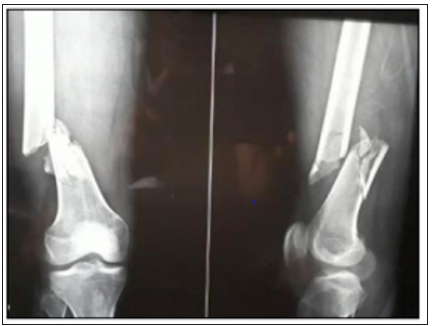

The incidence of distal femur fractures is around 37/100,000 patients per year [1]. Characteristically, two separate mechanisms of injury cause distal femur fractures. In the elder population with osteoporotic bone and susceptible soft tissue envelope, distal femoral fractures occur predominately after low energy trauma, e.g., falls and sprain injuries complicated by a high rate of comorbidity (60% female, older than 60 years). In young patients (60% male, younger than 40 years), high energy trauma causes complex injury with comminuted and open fracture pattern. Approx. 30% of patients with distal femur fractures are poly traumatized. 40% had soft tissue injuries, 10% had ligamentous lesions, 8% had meniscal lesions, 10% had dissected cartilage fragments and 15% had patella fractures and 38% of supracondylar/intercondylar distal femoral fractures have a coronal plane fracture [2-6]. Intramedullary femoral nailing has classically been performed using antegrade entry from piriformis fossa and has produced excellent results. Winquist et al had 99.1% union rate with postoperative knee ROM averaging 130degree and 0.9% infection rate [7]. Since antegrade nail has been so successful there has been resistance in surgeons to accept retrograde nailing as an alternative as shown in Figure 1 & 2; [8].

Figure 1: X-ray showed traumatic fracture at distal femur.